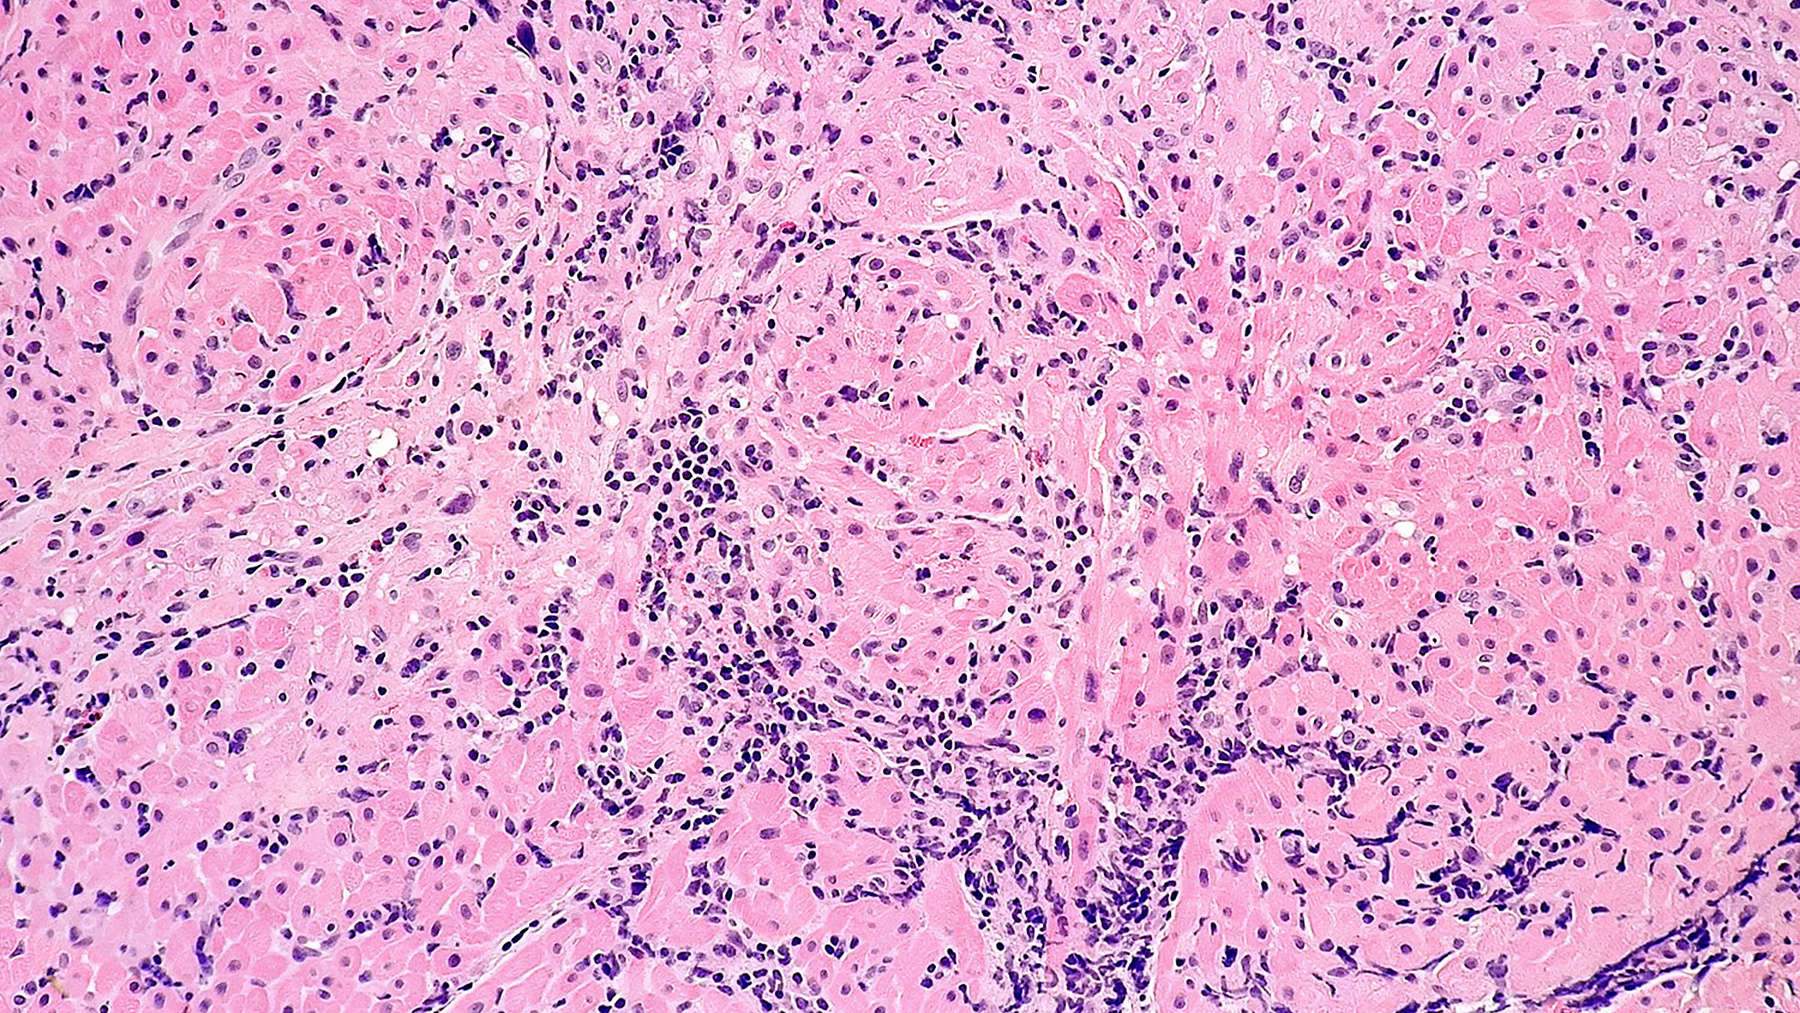

Acute Cellular Rejection: MODERATE

Figure A. H & E 20x

Clinical History: 64 year-old male with history of severe non ischemic cardiomyopathy, who received a orthotopic heart transplant.

Histology: H&E section (Figure A) of the myocardial tissue shows foci of perivascular mononuclear cell infiltration with some associated myocardial damage consistent with moderate acute cellular rejection (grade 2R) (ISHLT 1990 Grade 3A).  Special immunohistochemistry staining for CD3 and CD68 (Figure B and Figure C) show a predominant population of T cells and macrophages. Special stating for CD20 shows only a few scattered B cells (Figure D).